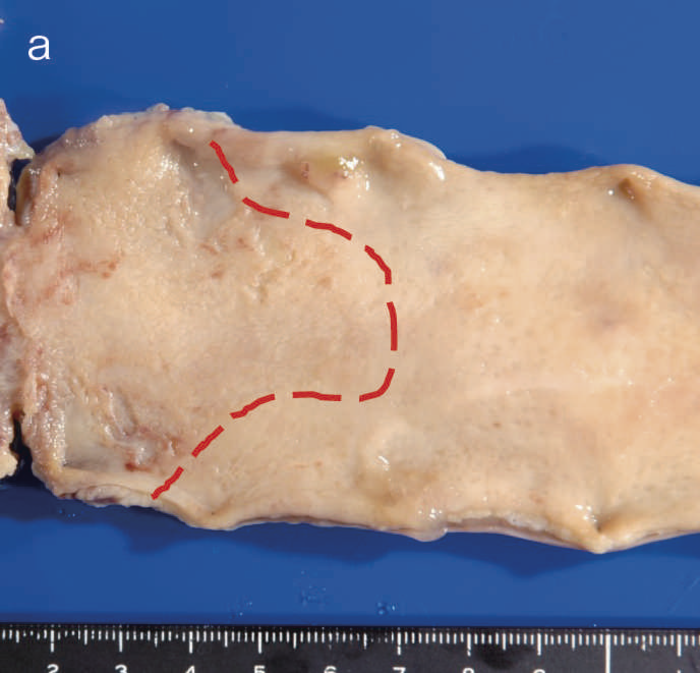

図6 UC関連LGDの内視鏡所見

- 白色光像:直腸(下部直腸)に色調変化は乏しく,微小な隆起を複数認めた。背景粘膜は寛解期にあった。

- NBI非拡大像:Brownishな領域が明らかとなった。

- 色素内視鏡像:病変辺縁が明瞭な微小な隆起を複数伴う表面平坦型病変。

- NBI拡大像:口径整でらせん状の微小血管と絨毛状の表面構造を認めた。

- pit pattern像:小型の類円形,管状pitを認めた。